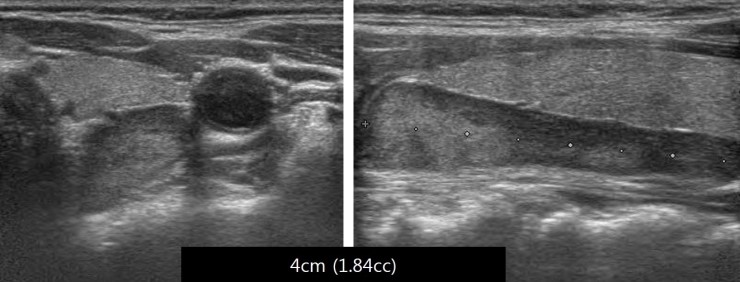

1. 부갑상선에서 발생할 수 있는 종양질환에는 어떤 것들이 있나요? ? 1) 부갑상선종 – 갑상선 상부보다 하부에 더 많고 크기가 다양하며 대부분 한쪽 부갑상선에 있음 – 크면 외부에서 만져지므로 식도벽에서 식도로 오인될 수 있음 결함 2) 부갑상선 증식증 – 원발성 부갑상선기능항진증 원인의 12-15%를 차지합니다. – 두 장애 모두에 다발 이상의 부갑상선이 관여하며, 4가지 모두에서 가장 흔함 – 가장 흔함 조직학적 소견은 주된 세포 증식이며, 이 경우에는 여러 내분비 신생물 증후군(MEN)3) 부갑상선 암종 – 매우 드물고, 약 200만 명 중 1명이며, 30세까지 발생하는 것으로 알려져 있습니다. 남성의 경우 – 혈중 칼슘 수치(14mg/dL 이상)와 부갑상선 호르몬 수치가 매우 높은 경우( 300 pg/mL 이상)이 관찰되는 경우 – 조기에 질병을 발견하고 수술을 제거하는 것이 가장 좋습니다. 5년 생존율이 50%, 10년 생존율이 10%로 예후가 좋지 않음 갑상선 수질암 2. 부갑상선 종양의 증상은? – 보통 원발성 부갑상샘기능항진증과 같은 “고칼슘혈증”에 의한 증상 동반 – 크기가 크면 겉으로 만져지는 경우 1) 신장 및 비뇨기 증상 – 신장결석에 의한 급성신통, 혈뇨, 농뇨 – 신석회증2) 골증상 – 골막하 미란, 뼈 흡수 및 연화, 연골 결석 – 관절통, 병적 골절, 뼈의 낭성 변화, 뼈 부분의 부종, 골밀도 검사 결과 부족 또는 뼈 골다공증 – 지속적인 피로, 식욕 부진, 근위부 근력 약화, 근육통, 일상 생활 장애 , 보행장애 3) 신경학적 증상 – 경미한 정서불안에서 정신병에 이르기까지 – 우울, 신경쇠약, 인지장애 매우 흔함 – 식욕감퇴, 삼킴곤란, 후각장애, 감각이상을 호소하는 청력소실 4) 소화기계 증상 – 소화성 궤양, 췌장염, 담석증 등 5) 고칼슘혈증에 의한 증상 – 다갈증, 다뇨증, 식욕부진, 구토, 변비, 근력약화, 피로, 의식변화, 피부건조 등 심하면 혼수상태에 빠지기도 하고 급성 신부전, 심부정맥으로 사망에 이를 수도 있다. 3. 부갑상선종양은 어떻게 진단하나? ? ? – 혈액검사로 부갑상샘호르몬, 혈중칼슘농도 확인, 혈중 인산, 비타민D, 소변칼슘, 혈중크레아티닌 등 검출 – 골감소증의 정도를 판단하기 위해 골밀도검사 적용 – 고칼슘혈증 다발내분비종양증후군 MEN 증후군은 반드시 환자의 가족력을 물어 확인한다. – 부갑상샘기능항진증은 2A 환자의 40%에서 발생 – 질환을 일으키는 부갑상샘의 위치를 파악하기 위해 초음파, CT, 동위원소 영상 등을 시행 할 수 있나요? ? – 부갑상선종양이 진단되어 수술을 계획하는 경우 수술 전 병이 생긴 부갑상선의 위치를 정확히 파악해야 함 – 특히 수술 중 재수술이나 재발 여부를 확인하기 어려운 경우에는 수술 전 평가가 매우 중요1) 초음파(US ) – 보고된 민감도 약 85%, 특이도 약 94%로 주변 갑상선 조직보다 옅고 잘 정의된 종양으로 관찰됨2) 경부 컴퓨터 단층촬영(CT) – 비교적 유용하지만 호흡기 또는 삼키는 동안 오류가 발생할 수 있습니다. , 보고된 민감도는 약 45%, 특이도는 98%3) 자궁경부 자기공명영상(MRI) – 부갑상선 선종에 대해 CT보다 민감도가 78% 이상 보고됨 4) 핵의학 스캔 테스트(1 ) Thallium: 갑상선과 부갑상선에 흡수 (2) Pertechnetate: 갑상선에만 흡수 – (1)에서 (2) 영상을 제거하여 영상을 얻는다. 87%라고 합니다. 민감도와 특이도는 약 85-100%로 보고되었습니다. 감별법 – 부갑상선의 자가형광 특성을 이용하여 수술 시 근적외선으로 “실시간”으로 부갑상선의 존재를 확인하는 기술이 개발되고 있습니다. 분자. 2019 Jul 14;24(14):2560 – 부갑상선 자가형광 – 부갑상선 및 갑상선 수술에 어떤 영향을 미칩니까? 경력 5년 5. 부갑상선 종양은 어떻게 치료합니까? – 치료를 위해서는 수술이 필요하며, 보조 요법과 약물 치료가 가능합니다! (내용을 보시려면 이전 게시물 참조 – 고칼슘혈증의 보조적 치료 및 약물치료) 1) 부갑상선 수술 시 고려해야 할 원칙 (1) 수술 부위 출혈이 없도록 해야 함 (2) 각종 수술 전 수술은 허용되지 않음 검사를 통해 부갑상선의 병리학적 위치를 맹신함 (3) 반회후두신경을 이용하여 수술 중 부갑상선의 위치를 추정할 수 있으며, 4개의 부갑상선이 모두 탐사에 의해 확인됨 (5) 수술 중 판단이 명확하고 외관상 정상임 부갑상선은 적출하지 말 것 (6) 동결 절편, 정상 부갑상선을 보존할 것 (7) 절제한 조직은 모두 동결 절편으로 할 것 (8) 부갑상선 조직은 동결하여 동결 절편에 보관할 것 부갑상선기능저하증 또는 수술 후 재수술을 위한 준비. 이비인후과(머리와 목) OtorhinoJaryngoJogy – 두경부 수술 – 군자출판사2) 부갑상선 수술 약 50 mg만 유지 (2) 전체 부갑상선 절제술 및 자가 이식 – 흉선과 함께 4개의 부갑상선을 모두 제거, 제거된 조직의 크기는 약 60~80 mg의 조직이 가장 작고 정상으로 보이는 부갑상선에서 채취됨 , 0.5–1.0mm 조각으로 자르고 흉쇄유돌근 또는 상완요골근에 삽입합니다. 절제 (4) 악성 부갑상선종양의 수술 – 주변 장기와의 유착이 있어 악성종양이 강하게 의심되는 경우 가능한 한 주변 유착구조와 함께 암을 절제해야 한다. (두경부) OtorhinoJaryngoJogy – 두경부 수술 – Gunja Press Surgical Encyclopedia – Parathyroidectomy6. 부갑상선 수술 후 알아야 할 중요한 사항이 있습니까? – 혈중 칼슘 수치는 수술 후 48시간 이내에 정상으로 돌아오지만 일부 환자에서는 저칼슘혈증이 발생하여 수일 내에 회복될 수 있습니다. 부갑상선 수술 전에는 명백한 뼈 질환으로 수술 후 혈중 칼슘과 인산염이 빠르게 뼈로 들어가고 저칼슘혈증이 오래 지속되며 심한 경우 Johns Hopkins Medicine – Bone Hunger Syndrome parathyroid ‘parathyroid’^^ 당신을 위한 부갑상선항진증, 부갑상선기능저하증, 부갑상선 종양 생소한 질환일 수 있지만 우리 이비인후과/내분비과 의사들에게는 매우 중요한 질환입니다! 칼슘 보충은 단순히 몸에 좋습니다! 정기적인 혈액검사를 하시는 것을 추천드립니다^^ 긴글 읽어주셔서 감사합니다, 다음에는 더 알찬 내용으로 준비해서 찾아오겠습니다! !